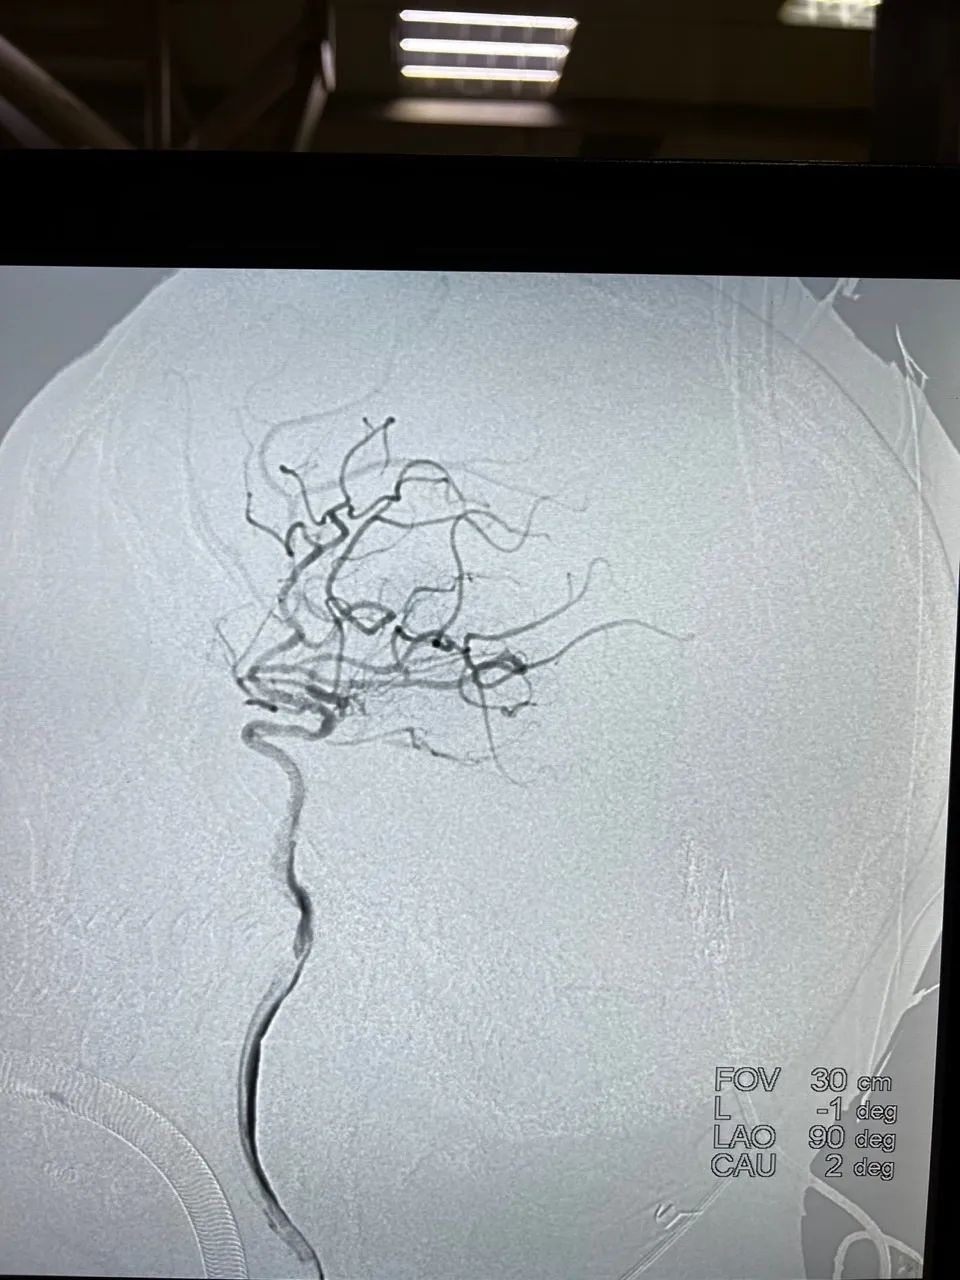

▲术前血管闭塞,血供受阻

术中,通过注射造影剂,可以发现患者的颈内动脉闭塞段很长,导丝前进非常困难,并且极易出现动脉夹层甚至误穿,一道道难关摆在了神经内科介入团队的面前。

手术艰难挺进,孟主任凭借精湛过硬的技术、丰富的临床经验,闯过一个个“关隘”,手术最终取得了圆满成功。

医生再次注射造影剂后,动脉造影显示,患者颅内半球成功恢复了循环血供,完美实现颈内动脉再通!

▲术后血流畅通